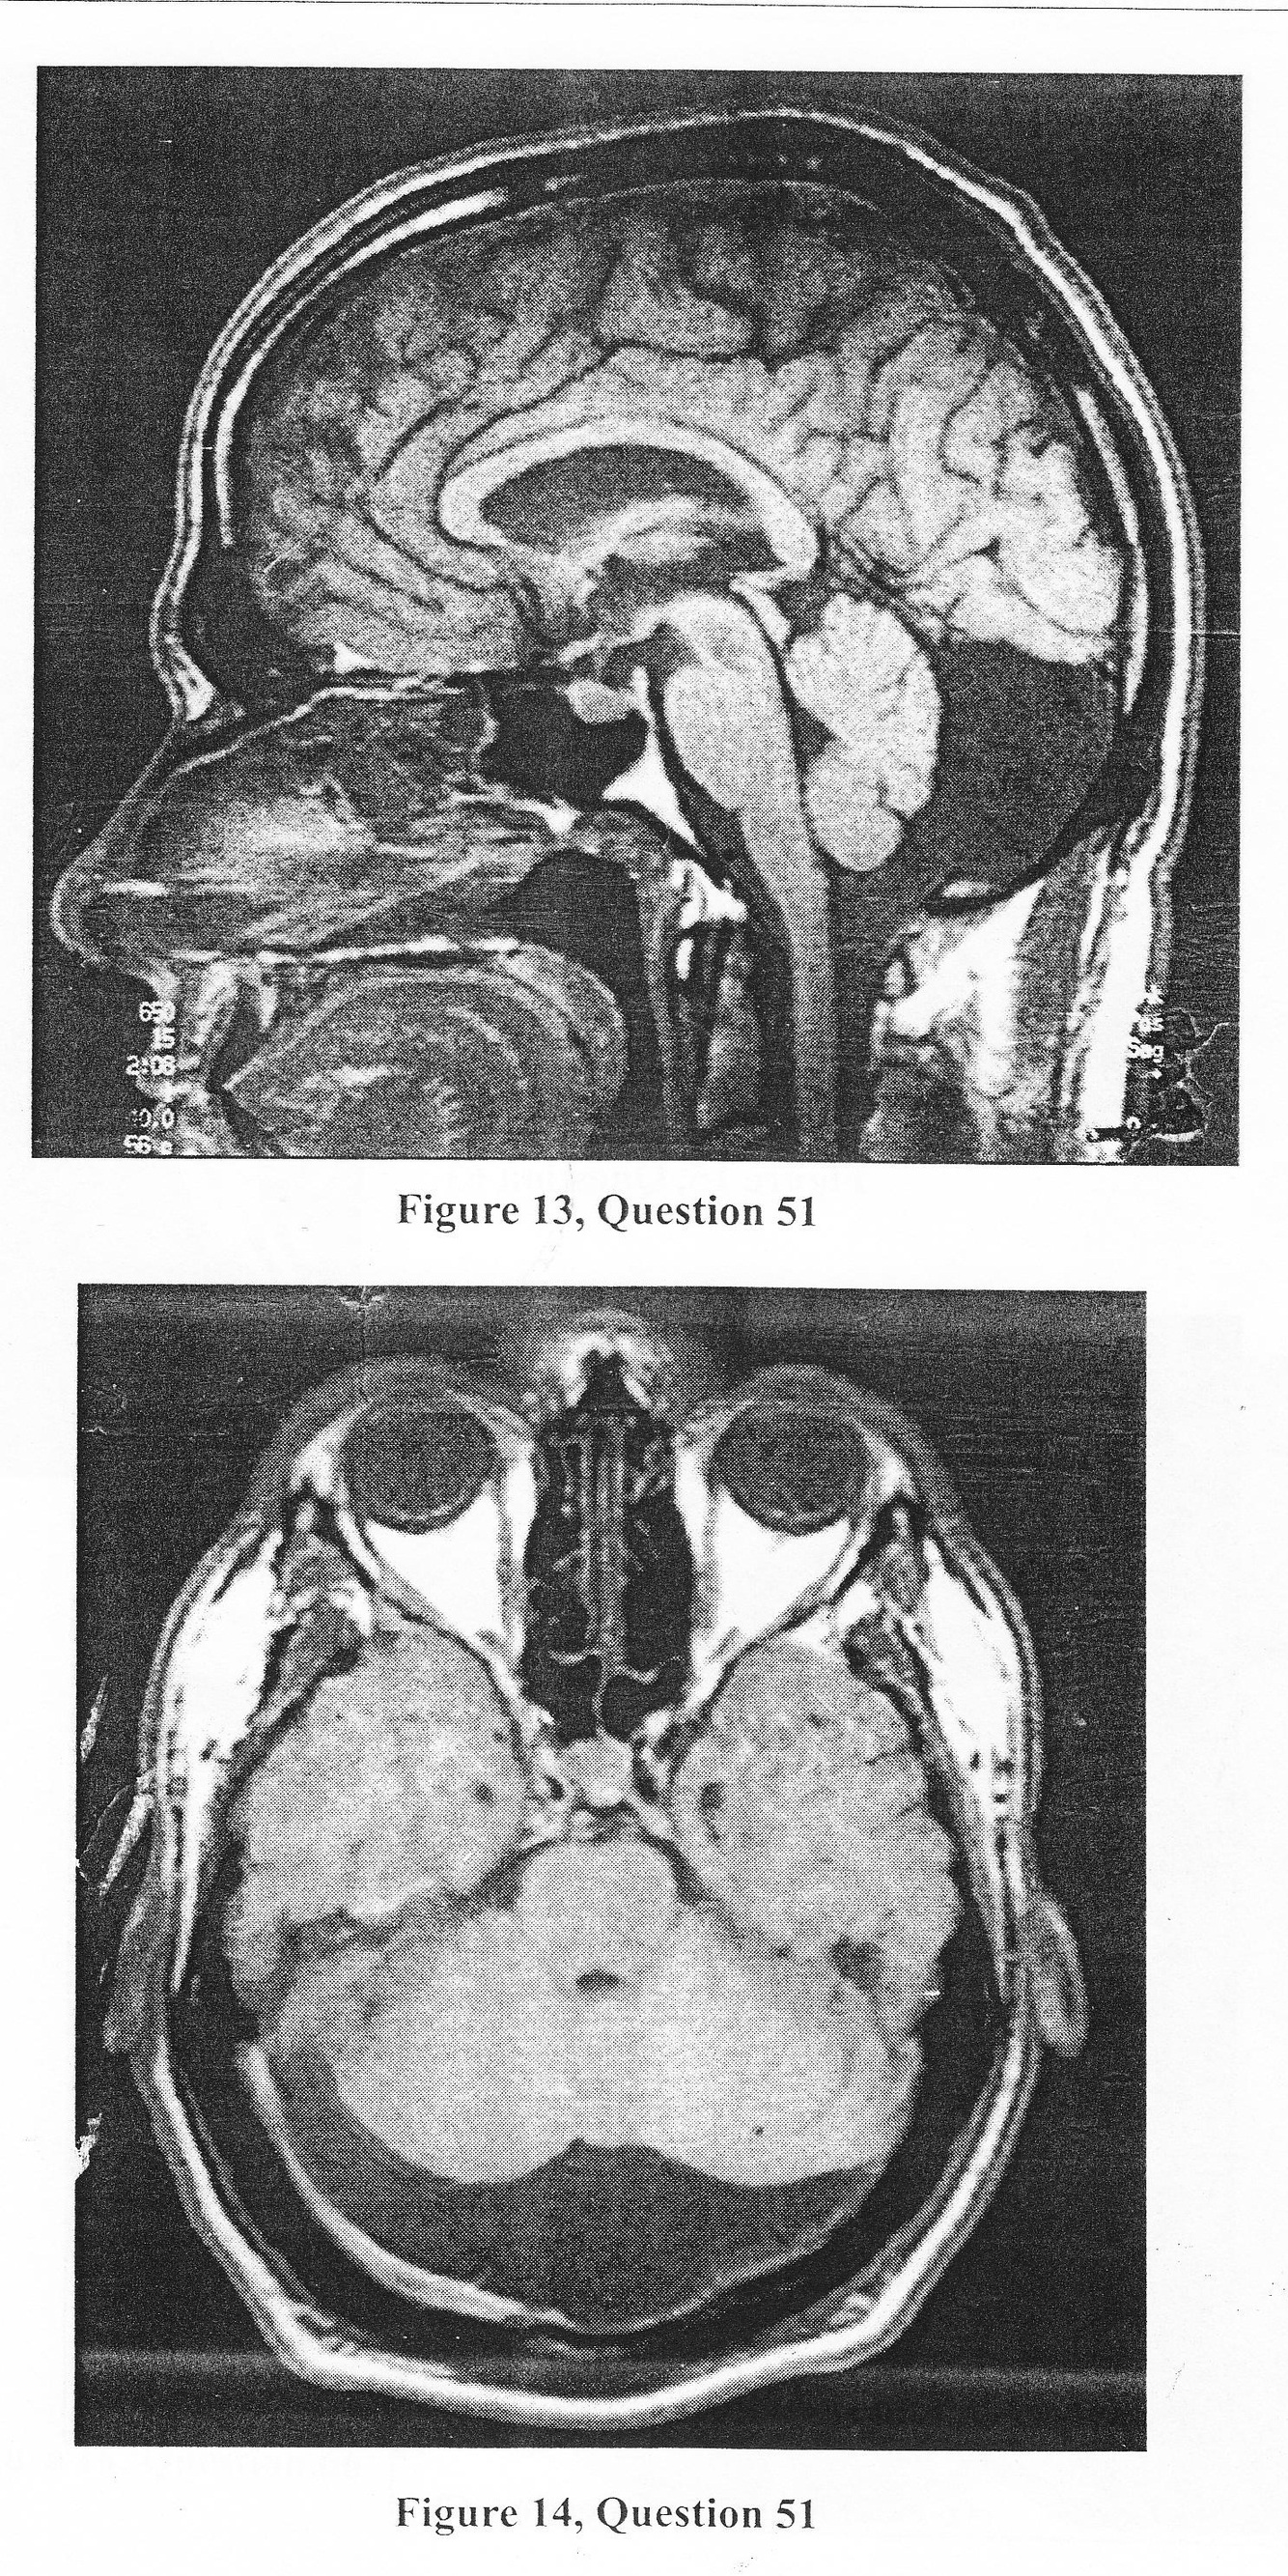

A.The differential diagnosis includes a mega cisternal cavity, retrocerebellar intra-arachnoid cyst, a Dandy- Walker malformation, and a Blake’s pouch.

B. The differential diagnosis includes a mega cisternal cavity and retrocerebellar intra-arachnoid cyst.

C. The MRI only depicts a mega cisternal cavity.

D. The MRI shows thinning of the occipital bone and deformation of the cerebellum.

E. Cisternography is not indicated.